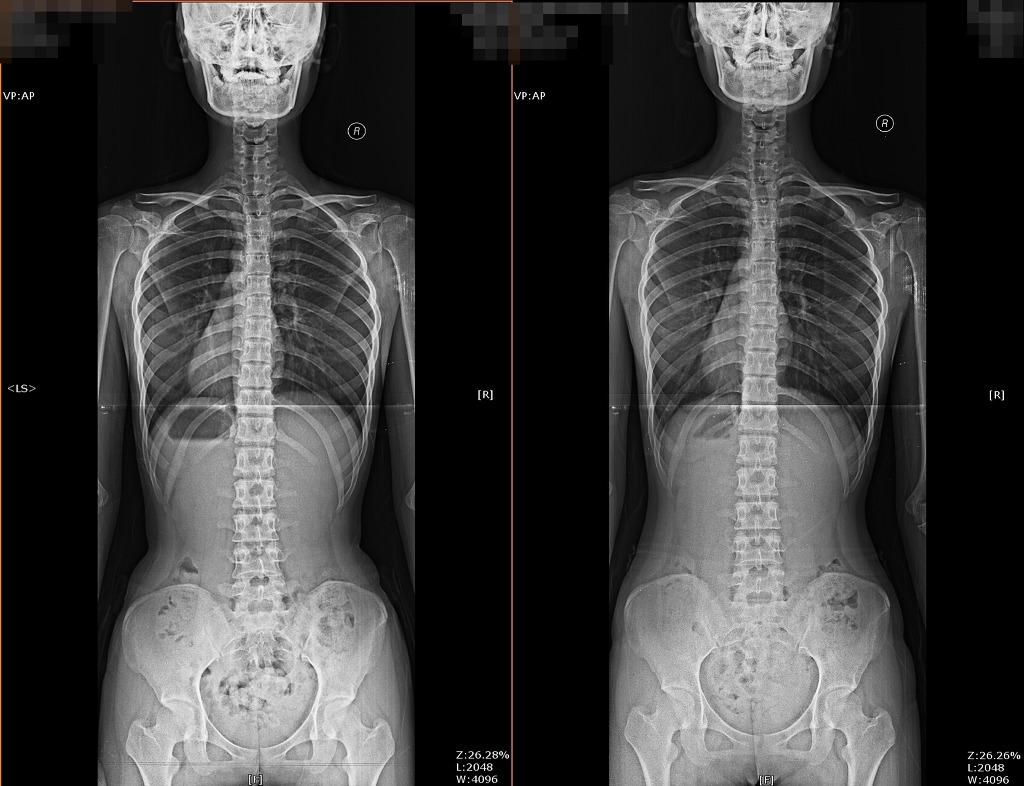

19세 여학생 골반교정사례입니다.

• 작성자MEMPT학회장 | 작성시간 12.04.02 요추 body rotation 이 좋아 젔내요,,보기 좋아요,,,

• 작성자신승용(총무이사) | 작성시간 12.04.03 pelvic cavity의 모양도 예뻐졌네요 ^ ^